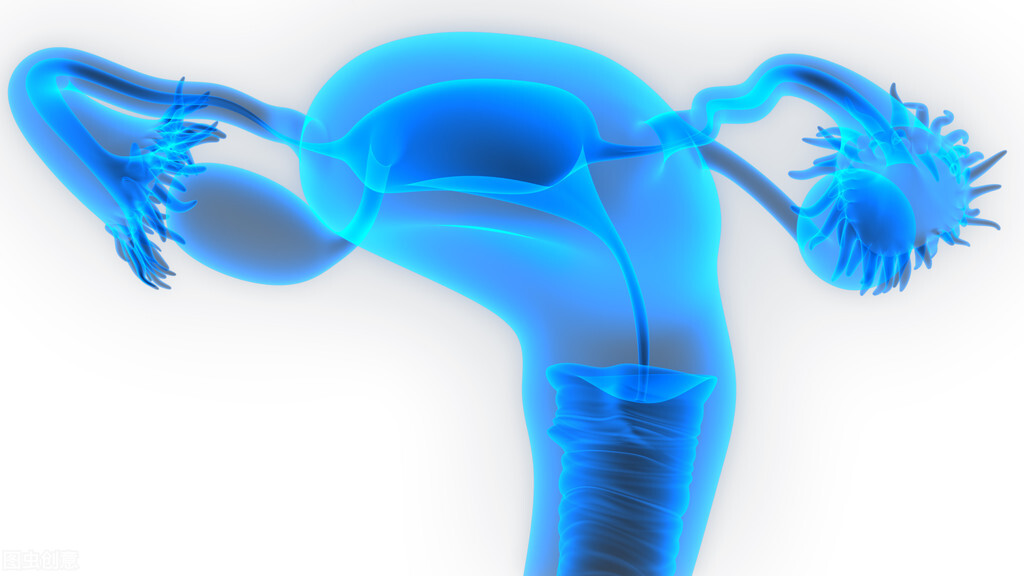

女人宫颈好不好,看1处是否有2个“信号”或能知道

子宫颈癌是目前威胁女性生命健康的一种比较严重的妇科疾病,而且近些年来也有逐年年轻化的态势。很多女性因为不能及时发觉子宫颈病变的“信号”,所以导致病情拖得越来越严重,甚至影响到生育能力,或者危及生命。

那么怎么知道宫颈好不好、健不健康呢?今天我们就来教大家看1处的2个“信号”:

那就是女性的私处。看是否有以下2个“信号”: